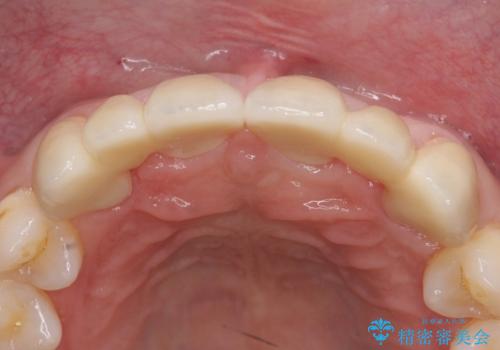

- 前歯部のすきっぱと歯並びが気になるので診て欲しいといらっしゃった方の症例です。

全顎矯正は御希望されなかったため、上顎前歯部のみの部分矯正とオールセラミッククラウンによる補綴を行いました。

今回用いたオールセラミッククラウンはジルコニアフレームという白い素材の上にセラミックを盛っているため、審美性が非常に高いのが特徴です。

また、ジルコニアは人工ダイヤモンドの材料にも使われているほど高い強度を持っており、そのためオールセラミッククラウンは審美性だけでなく、奥歯やブリッジの補綴も可能とするクラウンです。